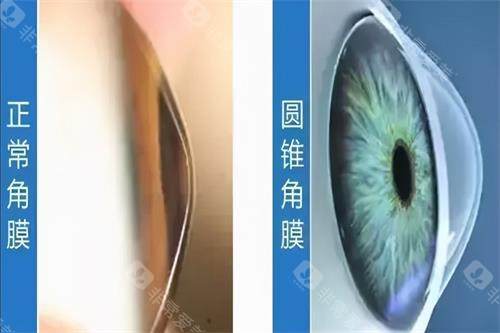

圆锥角膜是一种令人困扰的眼科疾病,而圆锥角膜交联手术为患者带来了希望。

视力改善的时间因人而异。大部分患者在术后1 - 3个月,视力会有一定程度的改善。

这是因为角膜交联手术后,角膜的形态逐渐稳定,屈光状态也会相应改变。